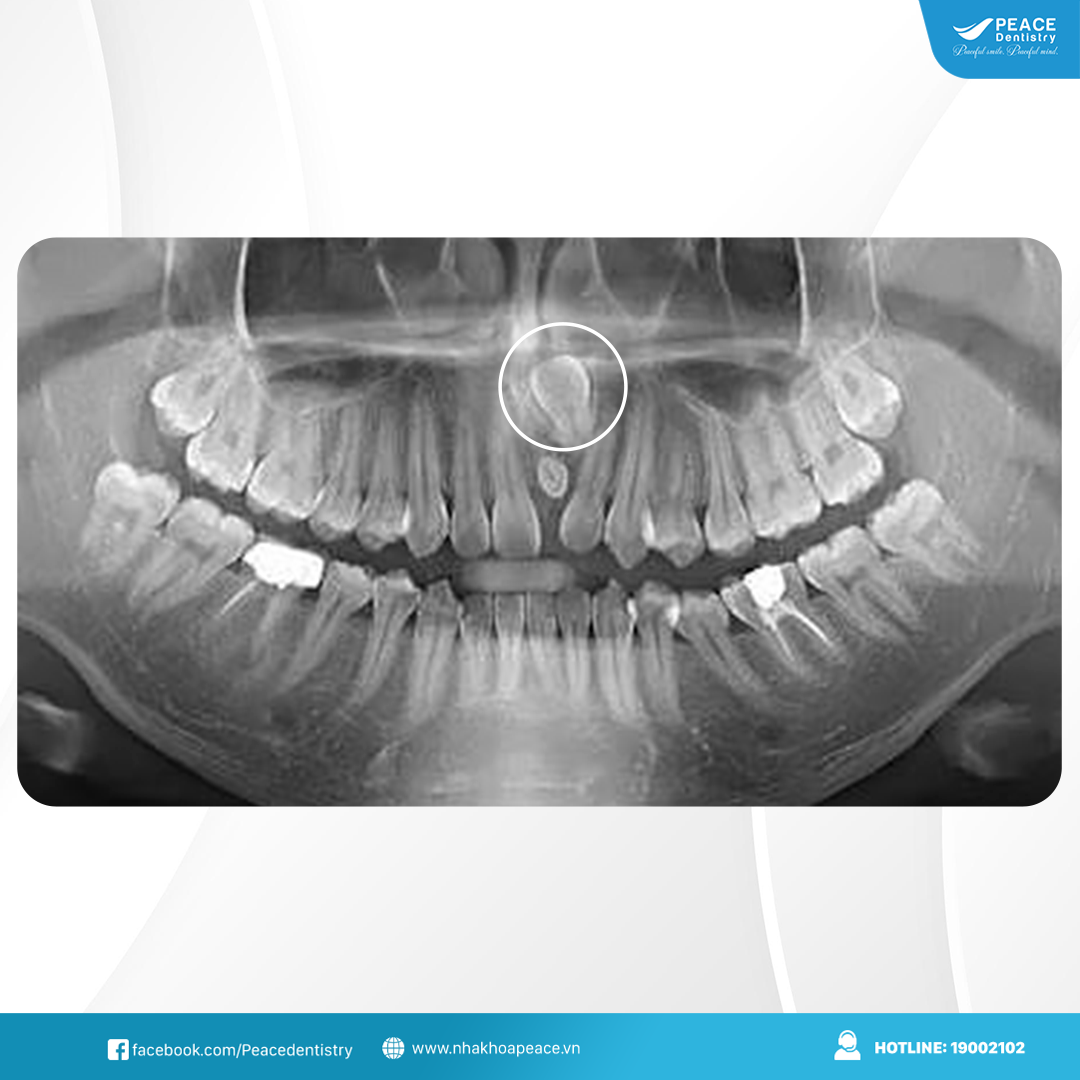

Không phải răng mọc ngầm nào cũng cần nhổ ngay. Nếu răng ngầm không gây đau nhức, không chèn ép răng kế cận hay ảnh hưởng đến chức năng nhai bác sĩ có thể chỉ định theo dõi định kỳ bằng phim X-quang. Điều này giúp kiểm soát sự phát triển của răng và can thiệp kịp thời nếu có biến chứng.

Kết luận: Răng mọc ngầm dù đôi khi không gây triệu chứng rõ ràng. Tuy nhiên, về lâu dài chúng có thể ảnh hưởng đến thẩm mỹ, sức khỏe răng miệng và gây ra nhiều biến chứng nguy hiểm. Việc thăm khám nha khoa định kỳ, chẩn đoán, chụp X-quang sẽ giúp phòng ngừa những rủi ro này. Vì vậy, nếu thấy có dấu hiệu bất thường bạn nên nha khoa uy tín để bác sĩ kiểm tra và can thiệp chữa trị kịp thời.